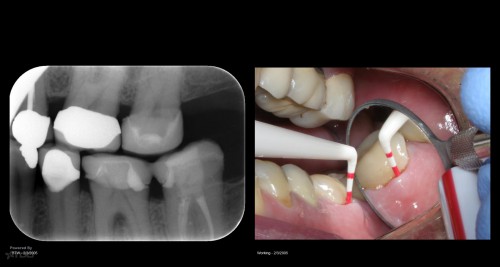

Disappointing recall

Busy recalling cases from the 10-15 yr time frame. Had I just done 5 yr recall, I’d never know …. gbc